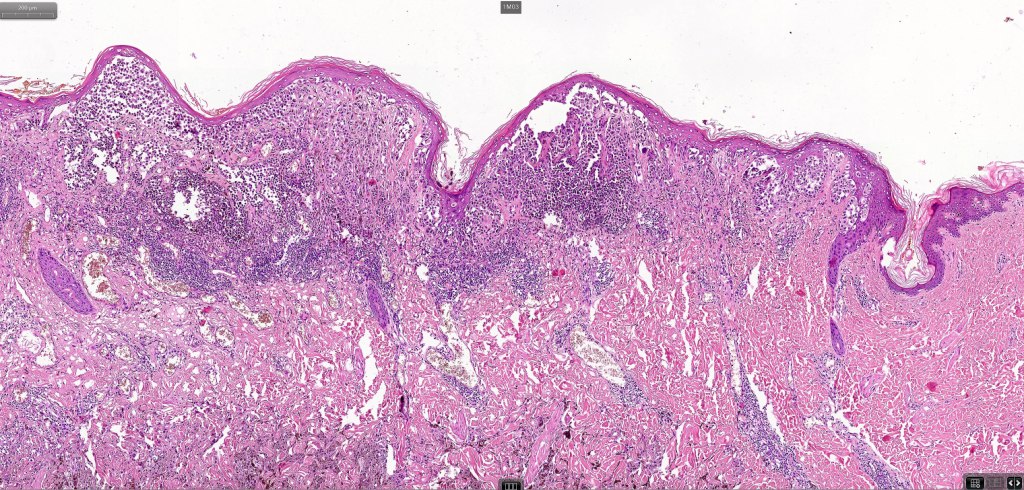

1.typical melanoma in the superficial aspect overlying a deep penetrating nevus-like deeper component

2. typical epithelioid melanoma in the superficial aspect associated with very marked perivascular and appendageal spread giving rise to a plexiform appearance

3. a deep penetrating nevus like lesion showing obvious signs of malignancy including greater pleomorphism than is usually seen combined with excessive mitotic activity, deep mitoses and atypical forms

4. melanoma which shows a deep penetrating architecture although the cytology remains epithelioid throughout